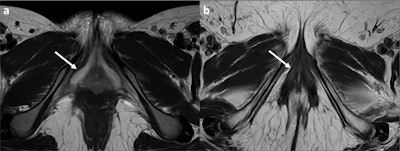

High-resolution axial T2 images show the clitoris (white arrows) of a 16-year-old post- pubertal woman (a) and a 73-year-old post-menopausal woman (b). In the younger woman, the clitoris is prominent and has a higher signal in T2 weighted images (WI); in the older woman, it is reduced in volume and has a lower signal in T2WI.